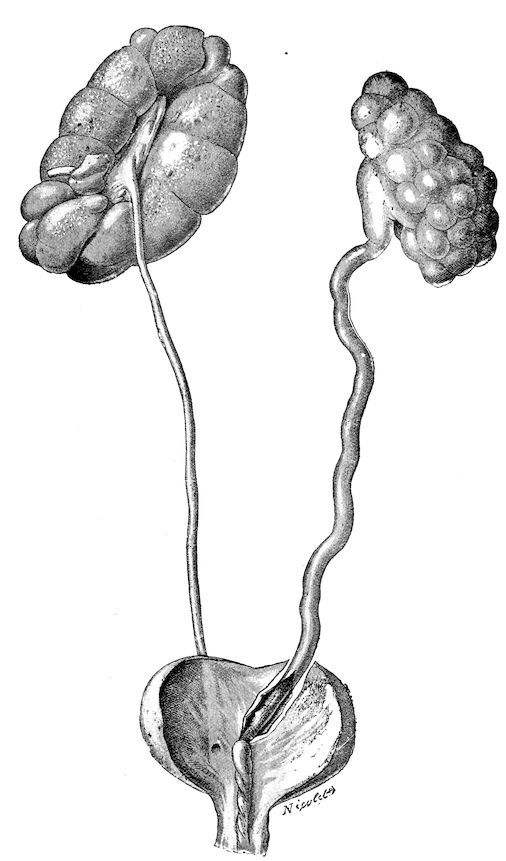

Fig. 1.—Rachitis in a young goat.